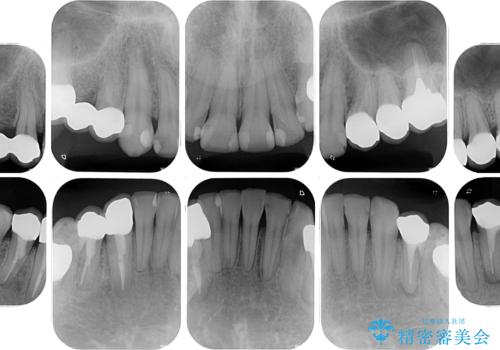

- 近医にて下顎奥歯の抜歯が必要と言われたとのことで来院された患者様です。

診察の結果、奥歯は左右ともに抜歯が必要な状態でした。

抜歯が必要な歯は事前に抜歯をし、その後ワイヤー装置にて歯列矯正を行い、途中でインプラントを埋入し、オールセラミッククラウンにて補綴治療を行うこととしました。

矯正治療にやや時間がかかりましたが、歯列はきれいに整い、気になっていたむし歯や銀歯は自然な色合いに仕上がりました。